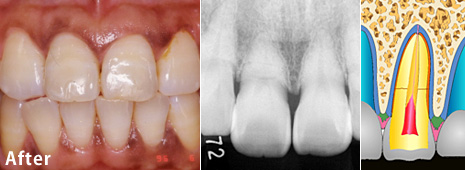

歯冠破折の治療例 その2

歯冠破折の治療例 その2 術前

術前:

8歳の少年の前歯がけがで2本折れました。歯の神経(歯髄)が露出していましたが、歯髄は生きています。

歯冠破折の治療例 その2 術後

術後:

上と同じ方法で治りました。